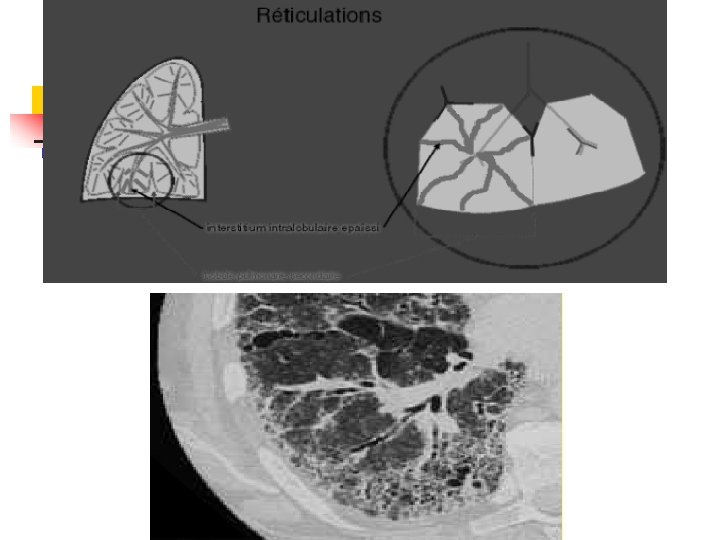

Réticulations Épaississement de l'interstitium intra-lobulaire n Petites opacités linéaires entrecroisées en une fine réticulation. n Mettent en connexion les opacités artérielles centrolobulaires avec les septa interlobulaires. n